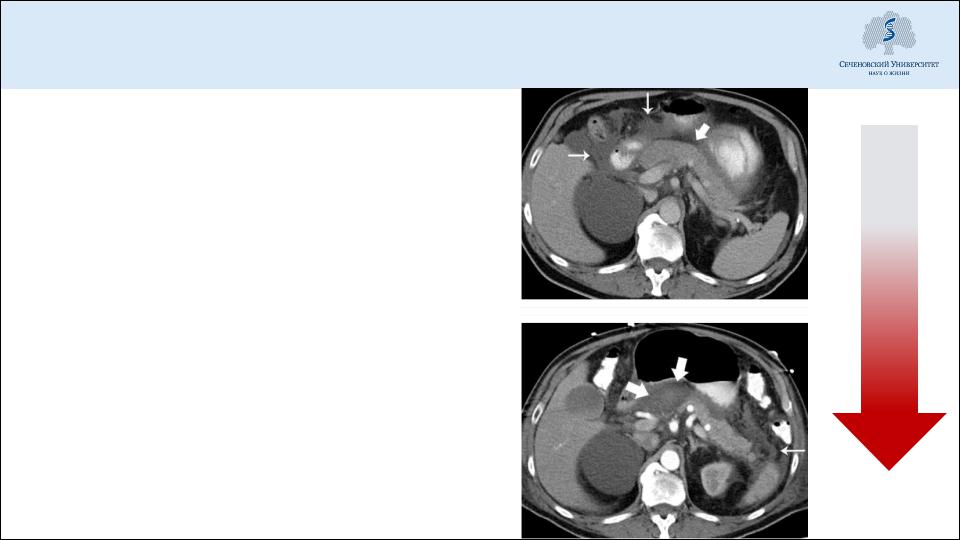

Диагностика: компьютерная томография

Выявление некрозов, их распространенности

Выявление местных осложнений панкреатита

Оптимальный срок выполнения – 72 ч от начала заболевания (время формирования некрозов)

При тяжелом остром панкреатите (панкреонекрозе) – динамическая КТ (раз в 7-15-20 сутки) для контроля воспалительного процесса, изменений в поджелудочной железе, забрюшинной клетчатке etc.a